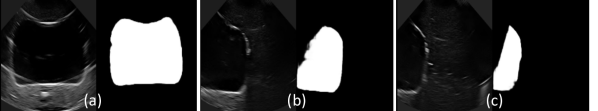

For the segmentation network, the qualitative results are shown in Fig. 9. We further evaluated this network quantitatively using the standard evaluation matrices, including Precision (P), Recall (R), F1 score (F1), Dice Coefficient (DC), and Intersection over Union (IoU). The values of these evaluation metrics for the 10-fold cross-validation and comparison with standard dice loss function (𝑳DCsubscript𝑳𝐷𝐶\boldsymbol{L}_{DC}) are given in Table II. The proposed loss function, 𝑳DJBsubscript𝑳𝐷𝐽𝐵\boldsymbol{L}_{DJB} outperforms 𝑳DCsubscript𝑳𝐷𝐶\boldsymbol{L}_{DC} on P, R, F1, DC and IoU by 3.2%percent3.23.2\%, 4.7%percent4.74.7\%, 2.6%percent2.62.6\%, 2.5%percent2.52.5\% and 4.8%percent4.84.8\%, respectively. Hence, the U-net guided with the proposed multi-loss function is an effective method for the segmentation of complex structures in the ultrasound image.

Refer to caption

Figure 9: The predicted masks when bladder appears (a) at full size, (b) approx. half of its size, and (c) one-fourth of its size